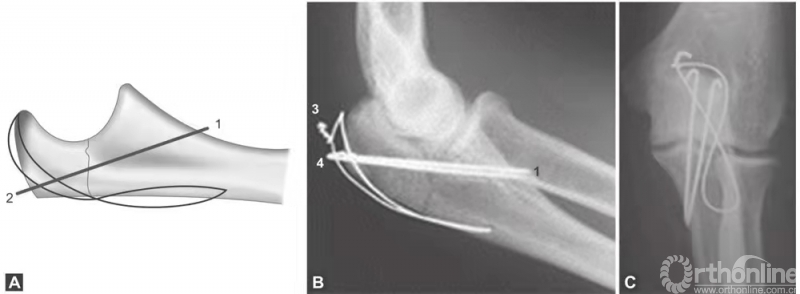

(图1A~C)为简单尺骨鹰嘴中部横形骨折,张力带钢丝可提供简单、便宜及有效的固定。

图1 A~C(1)克氏针应刚好只穿透前侧骨皮质;(2)张力带钢丝应放置在肱三头肌止点下方,在该部位打结,包埋;(3)张力带钢丝不应该在这里打结,因为它会导致皮肤损害和重度不适;(4)克氏针末端应在这里剪断,折弯并包埋

Weber -Vasey技术改良方法很多,有两个特别有用。一是使用长克氏针,到达尺骨髓腔的远端。尺骨髓腔的自然弯曲为直克氏针提供了可靠的三点固定,产生摩擦力,防止克氏针退出。二是克氏针贯通冠状突稍远端尺骨前侧皮质(图1A~C),使用该方法时,克氏针不得超过前侧骨皮质2~3mm,否则可能损害前侧的神经血管。两个方法中,近端克氏针和钢丝都必须很好地弯曲并包埋在鹰嘴尖端,以防止造成损害。

“8”字钢丝环应该放置在三头肌腱下面,而不是绕在克氏针的近端周围。使用宽口径导针可以使钢丝顺利穿过。在远端,钢丝环穿过2mm钻头在骨折线远端2~3cm钻的一个孔。钢丝环在鹰嘴尖端的近端拧紧,尾部剪断,弯曲并埋入肱三头肌腱下。钢丝应避免在尺骨边缘皮下拧紧和打结,否则会造成损害和不适。除了有经验的外科医生,术中常规用X线片检查关节的一致性和植入物的位置。